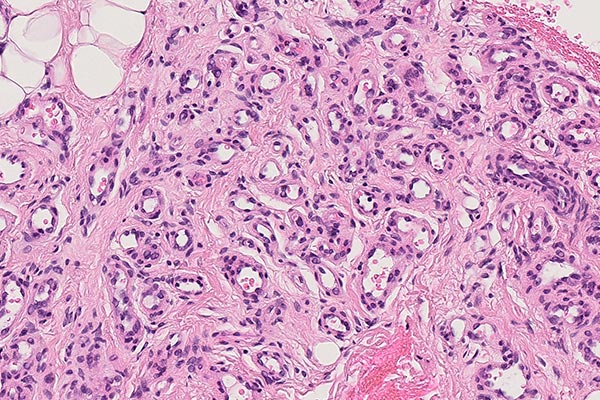

In der 90-fachen Vergrößerung (HE-Färbung) spricht die Lobulierung der Gefäßproliferate für einen benignen vaskulären Prozess. Die eingeschlossenen Skelettmuskelfasern sind zwar umwachsen, werden aber nicht destruiert, wie dies bei einem malignen Geschehen der Fall wäre. Die Vermischung mit präexistenten Gewebsstrukturen ohne deren Alteration ist typisch für infantile Hämangiome.

In der 270-fachen Ausschnittsvergrößerung (HE-Färbung) sind in der hier vorliegenden, beginnenden Involutionsphase die Lumina der Kapillaren innerhalb der lobulären Gefäßproliferate nicht schlitzförmig und sehr dicht gedrängt (was typisch für die Proliferationsphase wäre), sondern etwas dilatierter und zeigen echte Lumina. Die Kapillaren rücken auseinander zugunsten einer progredienten interstitiellen Fibrosierung und sind von Stroma umgeben. Zudem tritt eine Verbreiterung der Basalmembran auf.